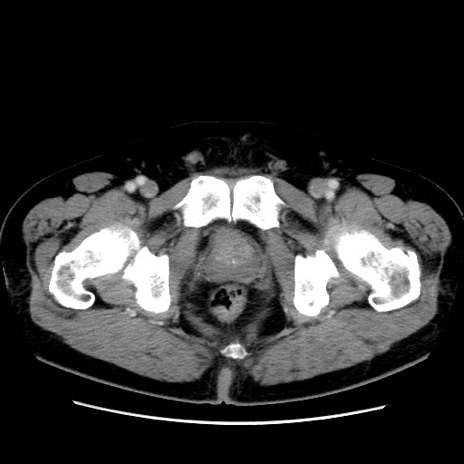

冠状断像